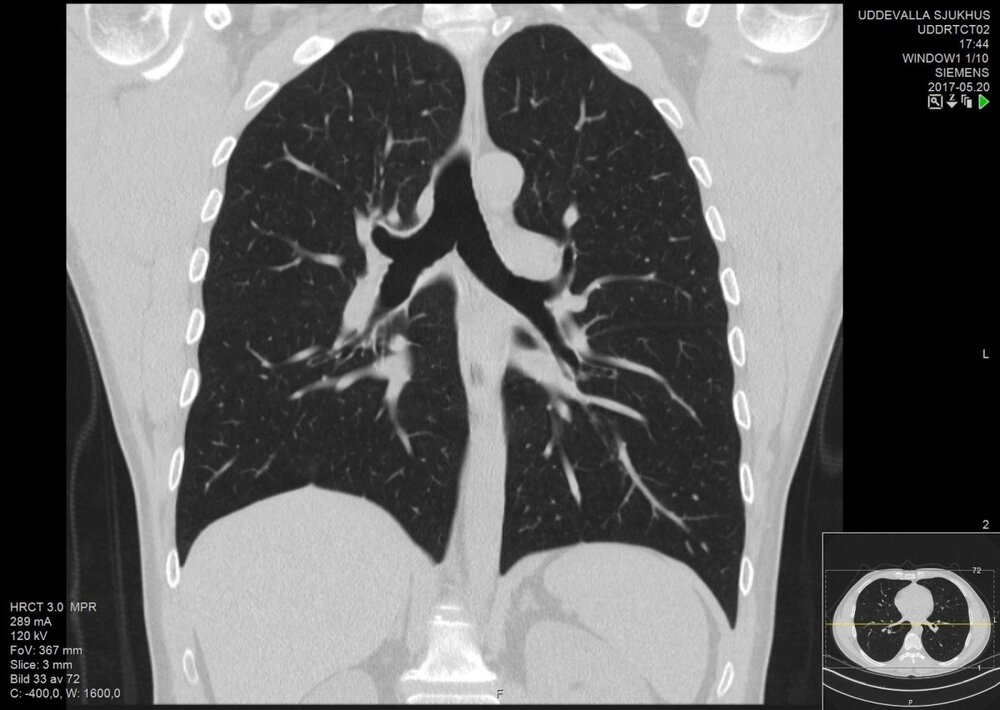

او میگوید: «برای پنج روز، بارها سرم زدم و آنتیبیوتیک مصرف کردم، اما حالم اصلا خوب نشد. روز هشت فروردین حالم به شدت بد شد، به سراغ همان پزشک رفتم و پس از بگومگویی او را قانع کردم تا آرمایش سیتی اسکن بدهم و از نتایج آزمایش فهمیدیم من به کرونا مبتلا هستم.»

پس از بررسی آزمایشها توسط پزشک مشخص میشود در دو هفتهای که کروناویروس وارد خانه شده بود به جز حسین چهار نفر دیگر هم از آن خانه ۳ طبقه به کروناویروس مبتلا شدند؛ مادر، عمه، شوهر عمه و پسر عمهاش. حسین چیز زیادی از آن روزها به یاد ندارد: «پزشک سیتیها را با دقت نگاه کرد و سریعا دستور داد که از بین ما ۵ نفری که مبتلا شده بودیم، من، عمه و شوهر عمهام در بیمارستان بستری شویم.»

پدرش، اما آن زمان خبر ترسناکی از پزشک شنیده بود که فرد دیگری از آن چیزی نمیدانست، او در حالی که اشک میریخت، میگوید: «پزشک گفت امیدی به حسین وجود ندارد، چراکه به دلیل تشخیص دیرهنگام بیماری نزدیک ۳۰ تا ۴۰ درصد ریههایش پر از عفونت شده بود.»